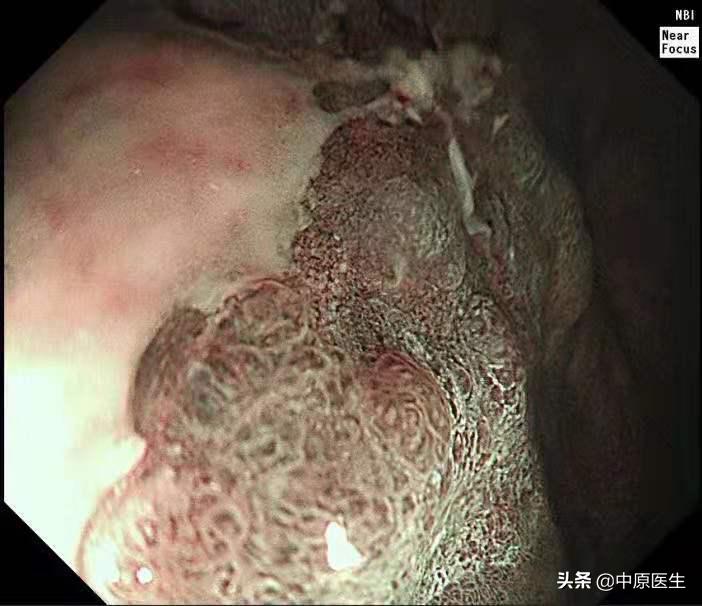

这个患者的溃疡多发,不算太大,并且表面的苔很干净,底部也算平坦,尤其是新发现的两个溃疡,从这几个条件来看,似乎良性可能性大。但是,我还是不放心。我现在只是用了白光检查,为什么不选择窄带光,放大检查?虽然麻烦一点,但是,可以看到更多细节!于是,我打开NBI模式,并且使用变焦(俗称放大,可以达到和显微镜下看类似的效果),再仔细地对每一处病变进行了观察,结果竟然发现,虽然范围很小,尤其是胃窦处的溃疡,不超过2个毫米的范围内我都发现了腺管缺失和血管异常扩张的地方,这往往提示病变有可能已经癌变,在放大镜的引导下,我对病变进行了精准活检。

周一上午,病理出来了,结果触目惊心,每一处溃疡都取到了癌组织,至此该患者诊断明确,他已经不是胃镜可以切除的早期胃癌,更不是良性的胃溃疡,而是需要进行外科手术切除的胃癌!